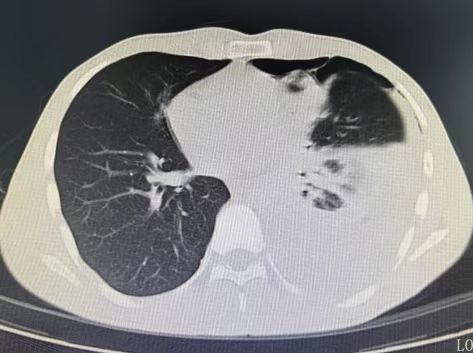

胸部CT检查结果让所有人警惕:小张左侧胸腔积聚大量浑浊积液,几乎占胸腔近三分之一,已压迫肺部引发气胸,不符合普通肺炎的影像学特征。当天,他就被收治入院。

确诊后,张先生接受了规范驱虫治疗,同时引流胸腔积液。一周后胸腔积液大幅减少;两周后CT显示积液基本吸收,肺部功能恢复正常,顺利出院。